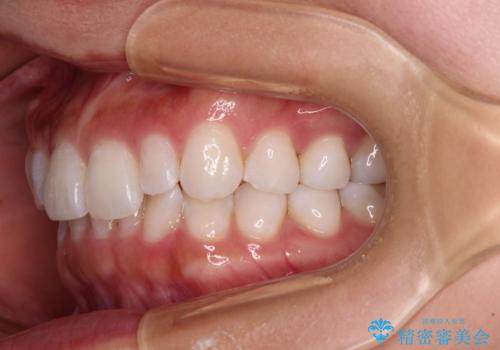

【モニター】前歯のデコボコと小さい前歯 インビザライン矯正とオールセラミッククラウン補綴治療

- 前歯の歯並びと生えてきたときから小さい前歯を気にして来院された患者様です。

上下前歯の歯列不正はインビザラインにより整え、その後に、矮小歯の前歯をオーダーメイドタイプのオールセラミッククラウンにて補綴治療することとしました。

インビザライン矯正の場合、矮小歯を矯正治療後にセラミックとするかどうかを矯正治療開始前に決める必要があるため、悩んでしまう方が多いです。

セラミッククラウンにて大きさを変更することを前提に矯正治療を開始したため、大変満足のいく仕上がりとなりました。